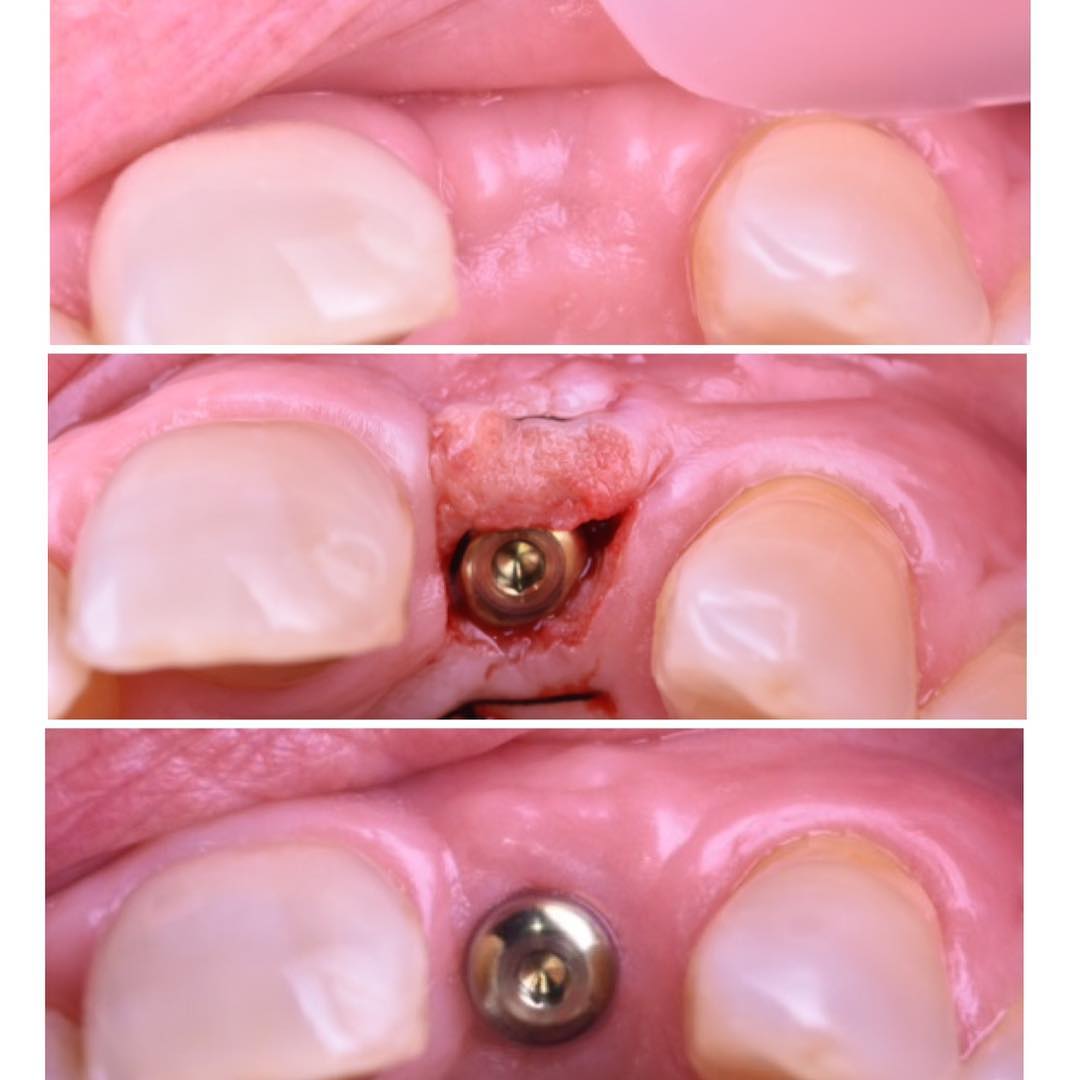

Caso de cirugía mínimamente invasiva en la que se realizó la exodoncia de una pieza dental seguida de la colocación de un implante inmediato mediante técnica flapless. Se utilizó un implante Klockner Vega+, priorizando la preservación del tejido blando y el mantenimiento del contorno alveolar. El implante obtuvo un torque de inserción de 50 N cm y valores de estabilidad (ISQ) de 76/80, lo que permitió realizar una carga inmediata con un provisional confeccionado previamente en clínica. Este abordaje favoreció la conservación del perfil de emergencia y la estabilidad estética desde el inicio del tratamiento. El procedimiento se desarrolló de manera predecible, con un resultado funcional y estético óptimo, manteniendo la integridad tisular y reduciendo el tiempo total de tratamiento.